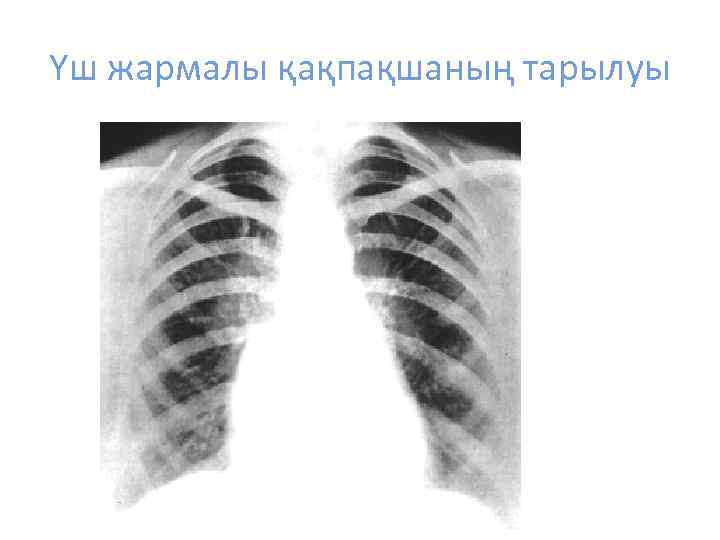

Үш жармалы қақпақшаның тарылуы